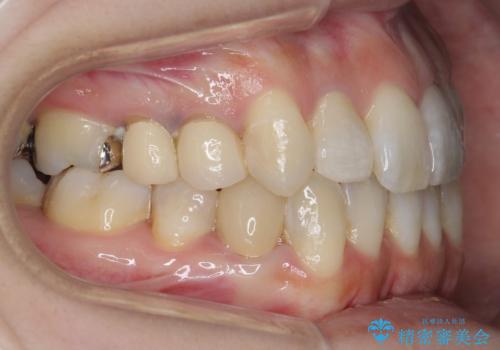

前歯のがたつきを主訴に来院。

ワイヤー矯正の古典的な治療方針である、4本抜歯して全体ワイヤーでも構わないとのことでした。

4本抜歯すると口元が下がりすぎてしまうため、下の前歯のみ1本抜歯および上顎の前歯が大きいため少し削らせてもらう提案をしました。

右上2番をしっかり並べるにはワイヤー矯正を上顎部分的に用いて、最後全体マウスピース治療を行いました。

上顎前歯は神経がない歯で色も変わってきていたためセラミックでかぶせています。